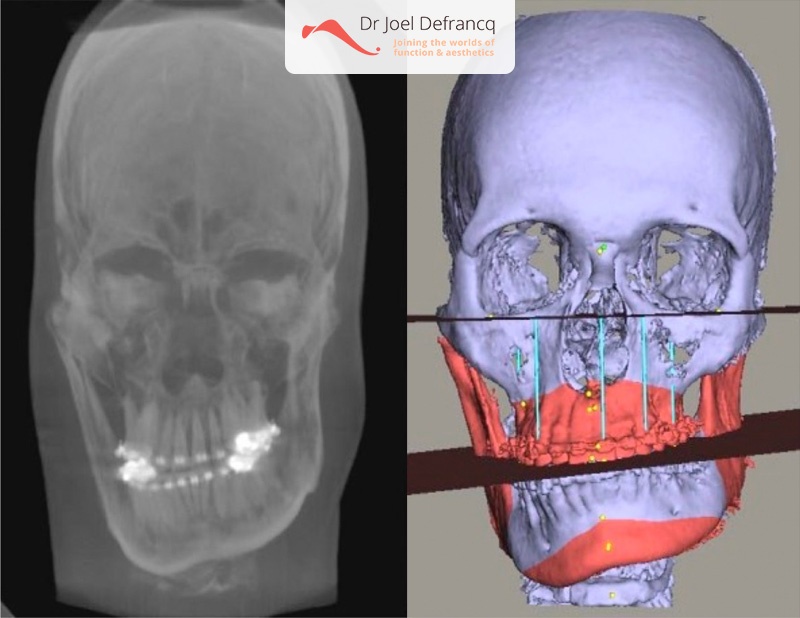

Orthognatische classificatie - Scheve kaken / Asymmetrische gezicht

De symmetrie van het gezicht beïnvloedt het oordeel over de esthetische kenmerken, de fysische aantrekkelijkheid en de schoonheid. Wanneer de asymmetrie van het gezicht duidelijk en storend wordt, is dit het gevolg van een abnormale groeiontwikkeling van de onderkaak. De onderkaak als botstructuur is inderdaad gevoelig voor asymmetrische ontwikkeling. Dit kan zijn ten gevolge van:

1. Abnormaal overvloedige groei van een onderkaakhelft, of mandibulakop of collum mandibularis. Een zijde wordt te groot waardoor asymmetrie overduidelijk wordt. Het midden van de kin wijkt af naar de onaangedane zijde. Kenmerken van condylaire hyperplasie kunnen eveneens zijn: posterieure open beet aan de aangedane zijde wanneer ontwikkeld tijdens de (late) adolescentie, of kanteling van het occlusaal vlak van de bovenkaak wanneer ontwikkeld op jongere leeftijd.2. Abnormale ondergroei van de mandibulakop (kop van de onderkaak). Het groeicentrum van de onderkaak, gelokaliseerd in de condyl, is beschadigd door trauma of infectie. Juveniele idiopathische artritis (JIA) en condylaire fracturen zijn ook veel voorkomende oorzaken van groeistoornissen van de onderkaak. Het groeicentrum van de onderkaak binnenin de condyl wordt vernietigd door trauma of inflammatoire ziekten. Beiden resulteren aan de aangedane zijde in een onderontwikkeling met een verschuiving van de kinpunt naar deze aangedane zijde. Er is eveneens een ernstige assymetrische retrognathische occlusie (Klasse II). Indien er juveniele artritis aanwezig is, zijn beide kanten aangetast en bestaat de kans dat de open beet met Klasse II zal ontwikkelen met ernstige retrognathie (teruggetrokken kaak). Er wordt met de behandeling gewacht tot de ziekte volledig is uitgedoofd, waarna orthognatische heelkunde kan volgen. Dit omdat asymmetrische ondergroei er het gevolg van is, waardoor één kant te smal wordt.

Malocclusie, kruisbeet en asymmetrie in het aangezicht. Deze aandoening creëert een variabel uitzicht dat zowel de occlusie, de kaken en het gezicht beïnvloedt. In de aangedane condyl kan de abnormale groei tijdens de jeugd van persisterende en blijvende aard zijn, of kan in verschillende golven verlopen.